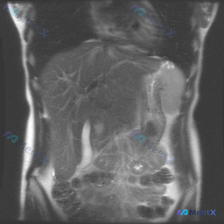

看到一份腹部MRI的影像分析,最初的问题是关于“脾脏病变”,但看完整个片子,觉得这远不止是脾脏的问题。整理了一下思路,和大家分享。 先看影像里的核心发现 这是一份腹部MRI-T2序列冠状位的影像: 1. 肝脏:形态不对,边缘是波浪状/结节状的(提示肝硬化);肝实质里有很多树枝状的高信号,是扩张的肝内...